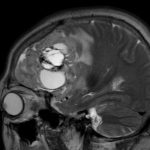

493

'23年12月

40代

頭蓋咽頭腫

頭蓋内腫瘍摘出術

No.’23_127 手術前1

No.’23_127 手術前2